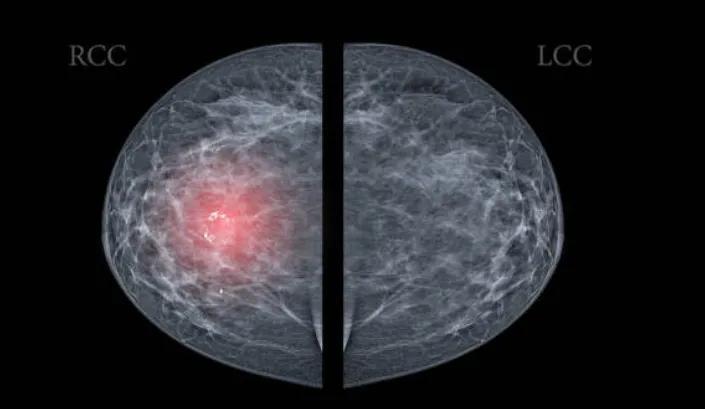

乳腺超聲報告,標註“不典型增生”

乳癌發展就像“種子發芽”,最初可表現爲乳腺導管或小葉不典型增生。但反過來,並不是所有的乳腺不典型增生都會癌變。

重慶大學附屬腫瘤醫院腫瘤內科主任王東林提醒,這類增生雖不具有典型的乳腺癌臨牀特徵,但也多表現爲乳房腫塊、乳頭溢液,或腫塊和溢液同時存在。

• 遵醫囑定期複查:一般不超過6個月就應複查一次。如果存在乳腺癌家族史,更需警惕。

• 避免不良情緒堆積:乳房是情緒的一面鏡子,壓抑、鬱悶都會傷害乳腺。

• 不亂用雌激素:乳腺是雌激素的靶器官,不濫用避孕藥物。

• 減少高脂飲食:高脂飲食易使雌激素水平升高,刺激乳腺細胞過度增生。